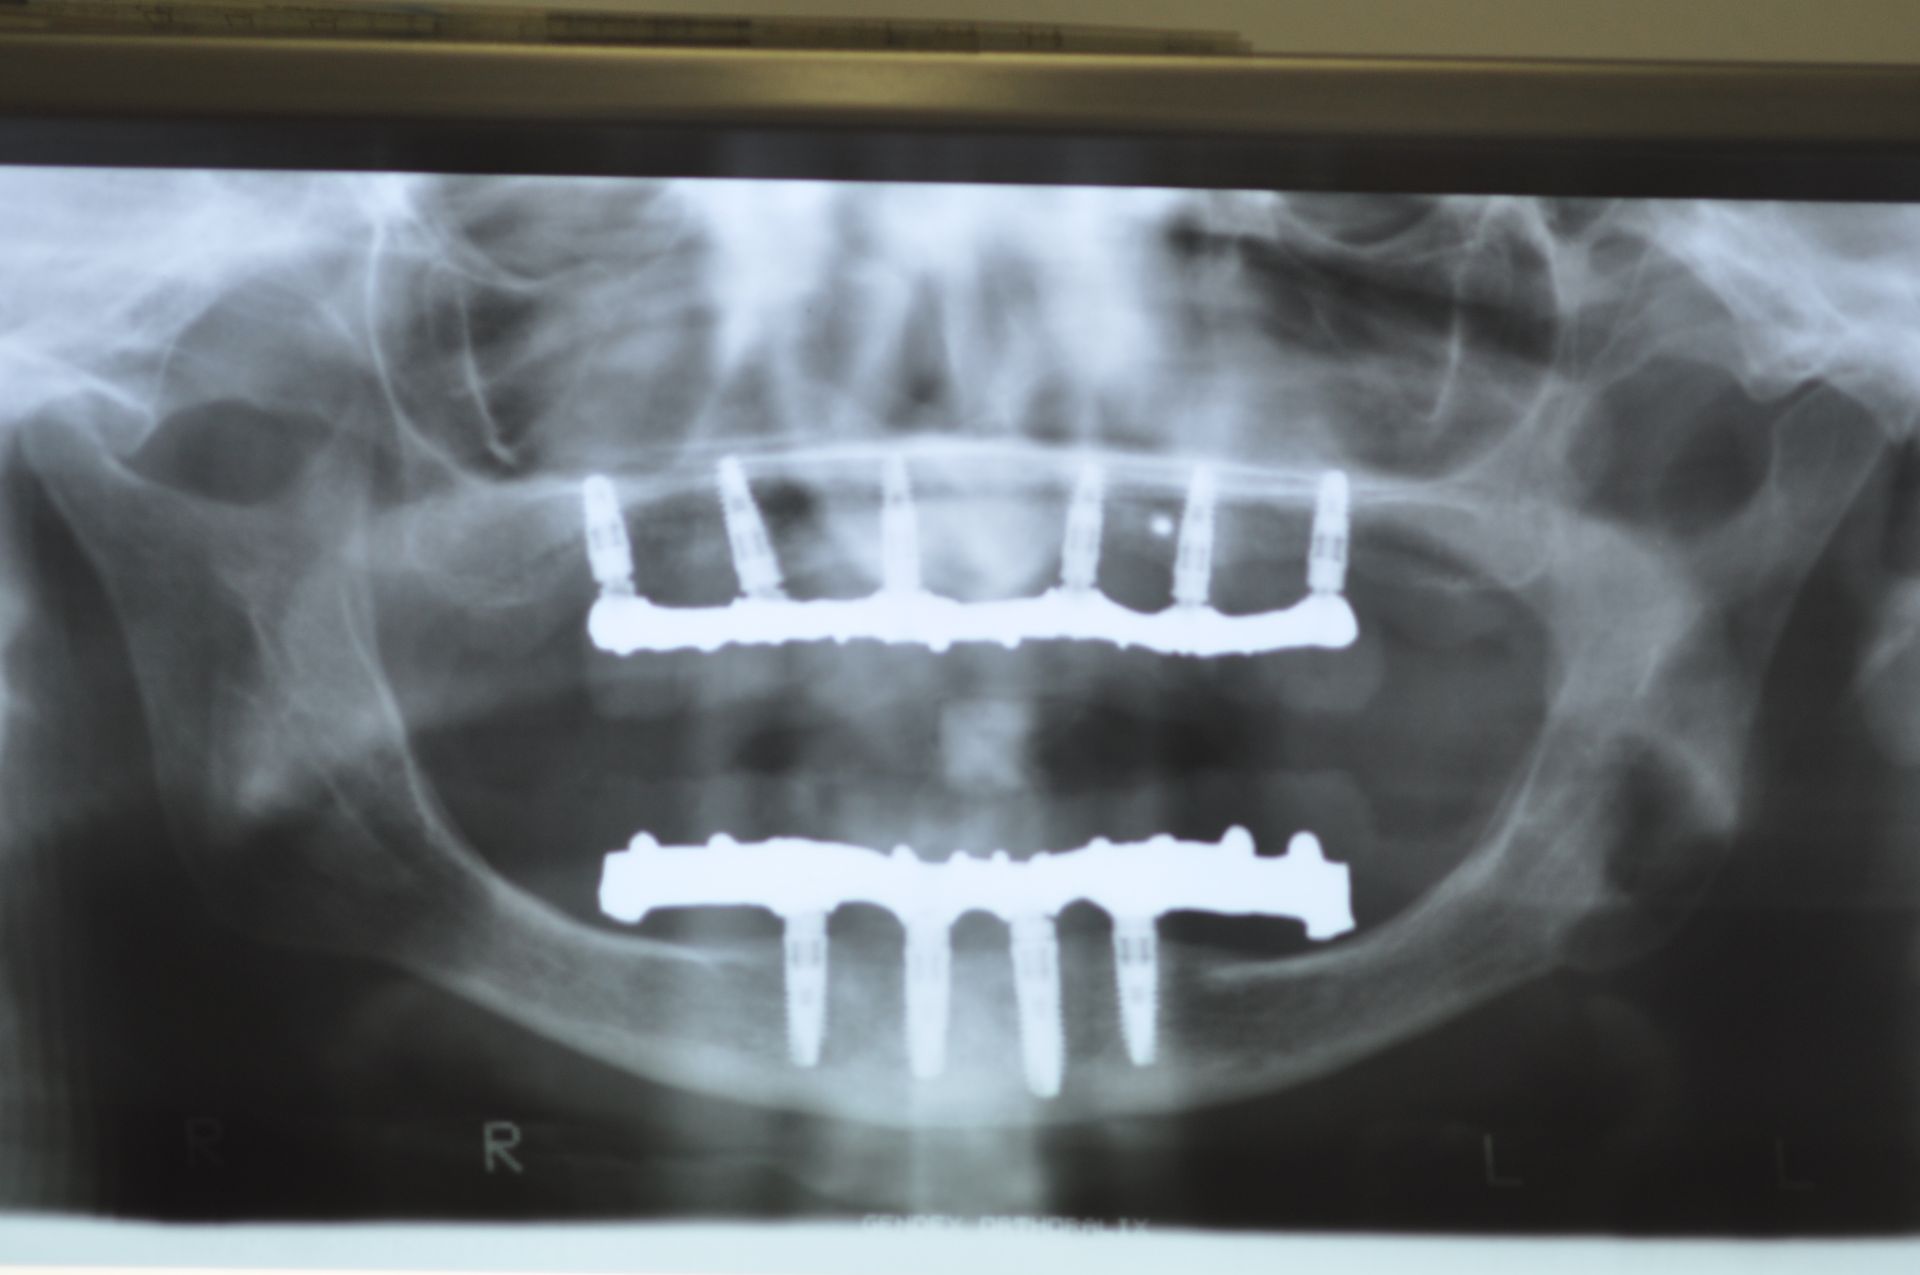

Implantologia

L'implantologia è una branca dell'odontoiatria che si occupa della sostituzione dei denti mancanti attraverso l'inserimento di impianti dentali. Questi impianti, realizzati in titanio biocompatibile, fungono da radici artificiali su cui vengono fissate protesi dentarie come corone, ponti o dentiere. L'implantologia offre una soluzione stabile e duratura per ripristinare la funzionalità masticatoria e l'estetica del sorriso, migliorando significativamente la qualità della vita dei pazienti.